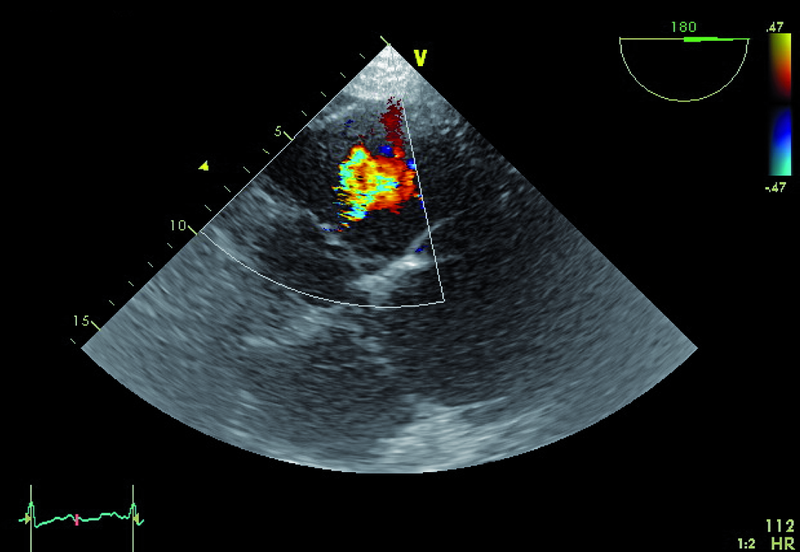

Kobieta, lat 73. Jakie patologie można rozpoznać na rycinach?

3. Powiększenie jamy prawej komory (ryc. 2).

4. Płyn w jamie osierdzia (ryc. 2).